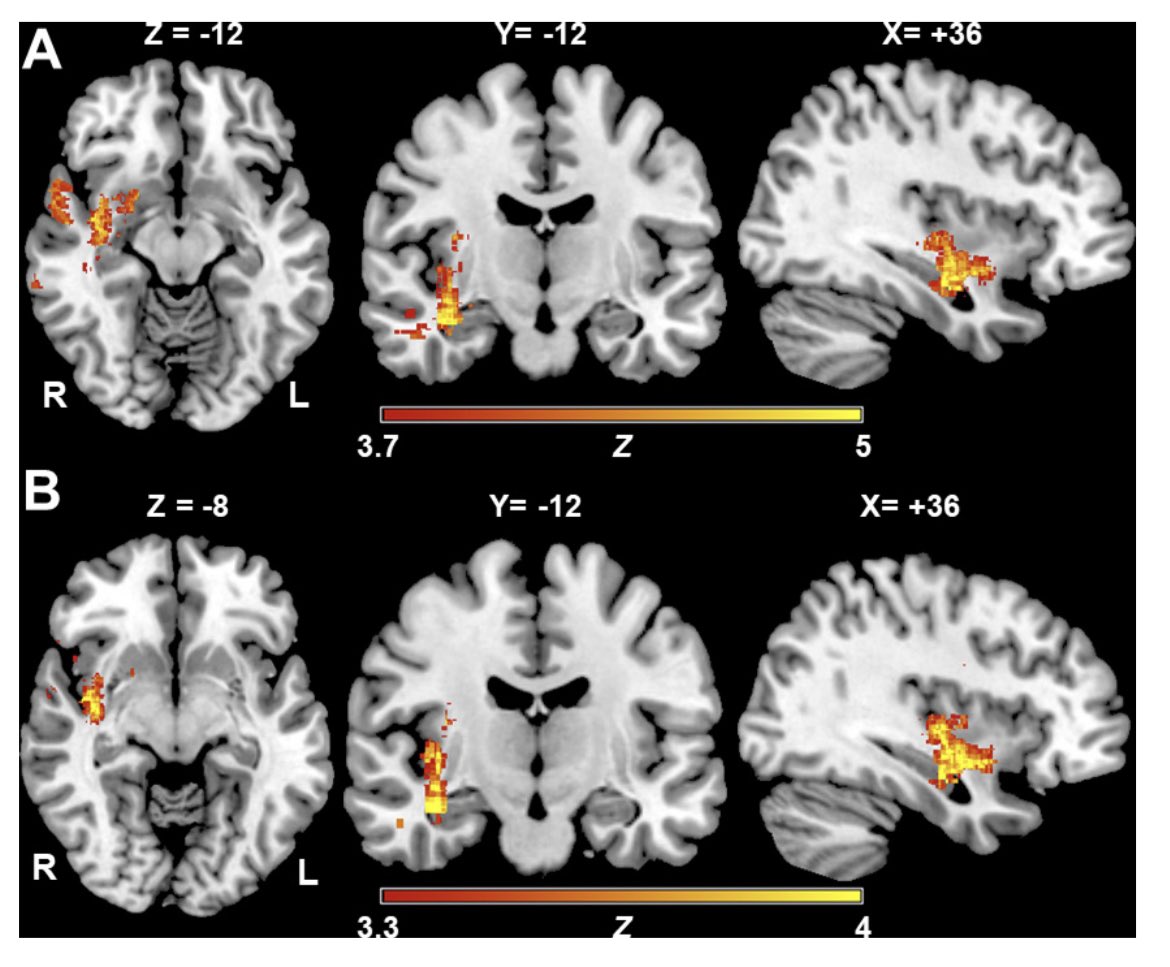

🚨Location Matters after Stroke Lesion location after #stroke dictates corticospinal excitability patterns linked to motor skill acquisition, with descending corticospinal pathway lesions primarily driving these associations. Check our pre-print here: medrxiv.org/content/10.110…

🚨Location Matters after Stroke

Lesion location after #stroke dictates corticospinal excitability patterns linked to motor skill acquisition, with descending corticospinal pathway lesions primarily driving these associations.